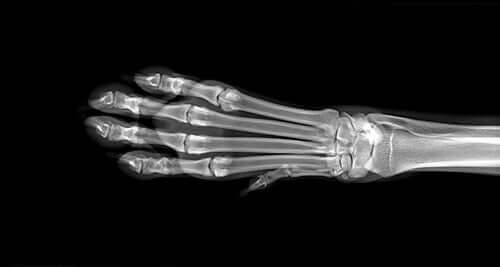

När du tar din hund till veterinären kommer han först att genomföra en serie diagnostiska test för att identifiera orsaken till svullnaden. Dessa kommer att inkludera blod- och urintest och eventuellt röntgen av benen. Om dessa tester inte indikerar något speciellt, kanske din veterinär vill göra en MRT-undersökning. Om veterinären misstänker att det är osteosarkom kommer han att utföra en benbiopsi.